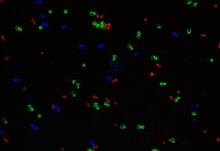

Using deep learning to improve rapid cellular imaging

Researchers have combined neural networks with a wide range of microscopy techniques to improve how scientists peer into cells